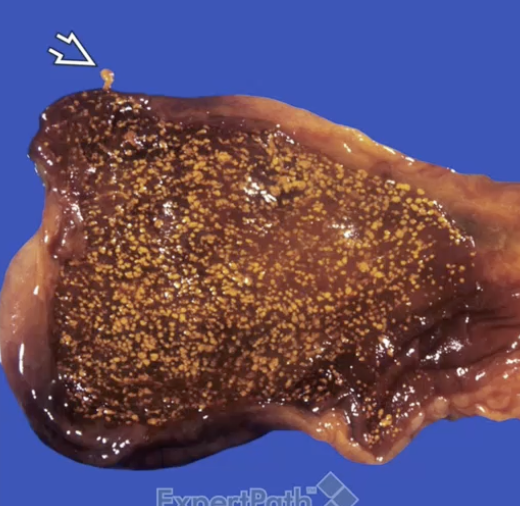

Cholesterolosis

Cholesterolosis